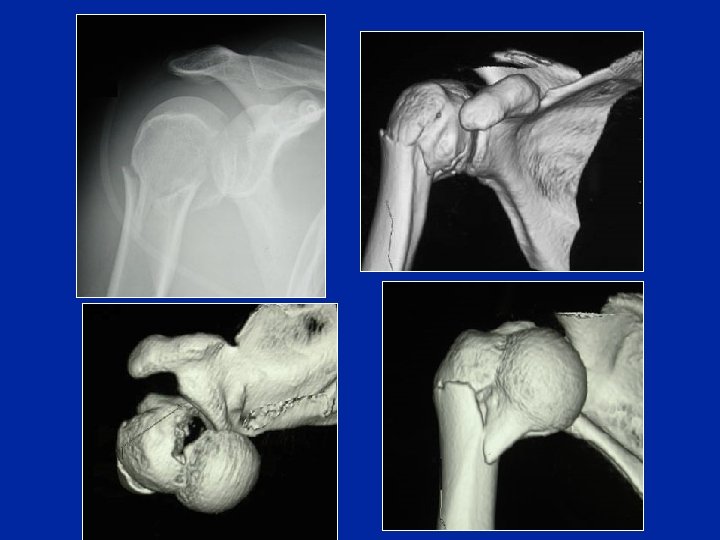

Fractures-luxations

Énucléation

Un cycliste tombe violemment sur le moignon de l’épaule. Il est très pâle mais conscient. C’est la première fois qu’il a un traumatisme de l’épaule. L’épaule est douloureuse et il est incapable de la mobiliser. Le membre supérieur est bloqué en abduction et rotation externe. A l’arrivée à l’hôpital l’épaule est tuméfiée et l’hématome qui est important gène l’examen clinique. La mobilisation passive de l’épaule est très douloureuse. Il existe une insensibilité du moignon de l’épaule. Les pouls périphériques sont perçus. Q 4 Quelle est votre conduite thérapeutique ? 1/ Si la radio ne montre pas de fracture du col huméral Réduction de la luxation (soit tentative de réduction lente, soit réduction sous AG) radio de contrôle 2/ Si la radio montre une fracture du col huméral Hospitalisation, bilan préop Réduction chirurgicale et ostéosynthèse de la fracture (plaque vissée ou clous élastiques) Immobilisation attelle 3 semaines puis mobilisation douce

Un cycliste tombe violemment sur le moignon de l’épaule. Il est très pâle mais conscient. C’est la première fois qu’il a un traumatisme de l’épaule. L’épaule est douloureuse et il est incapable de la mobiliser. Le membre supérieur est bloqué en abduction et rotation externe. A l’arrivée à l’hôpital l’épaule est tuméfiée et l’hématome qui est important gêne l’examen clinique. La mobilisation passive de l’épaule est très douloureuse. Il existe une insensibilité du moignon de l’épaule. Les pouls périphériques sont perçus. Q 5 Vous le traitez et pourtant son épaule devient raide et douloureuse dans les semaines suivantes, de même que son poignet alors que le moignon de l’épaule est redevenu sensible et non atrophié. Quelle complication secondaire vous évoque ce tableau ? Syndrôme épaule-main: algodystrophie du membre supérieur Phase chaude (pas de troubles trophiques)